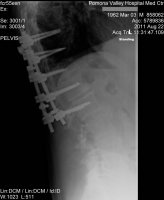

Me and my family Dr. were out in the Freemont area going from the Husky Monument over to inscription canyon. He fell and broke his collarbone. Had to ride his bike the 25+ miles back to the truck. On the way home he's making phone calls. We get home at 5:00, he's getting wheeled into the OR at 8:00 and in recovery at 1:00am. 17 screws and a plate later....